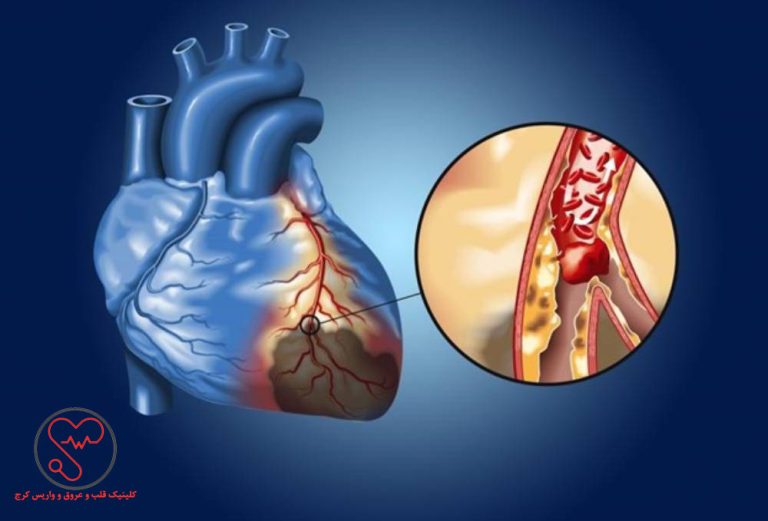

سکته قلبی یا انفارکتوس میوکارد زمانی رخ میدهد که جریان خون به قلب به شدت کاهش پیدا کند یا مسدود شود. این گرفتگی معمولاً پیامد جمع شدن چربی، کلسترول و مواد دیگر در شریانهای کرونری قلب است. به رسوبهای چرب و حاوی کلسترول پلاک گفته میشود. اصطلاح پزشکی برای فرایند تجمع پلاک تصلب شرایین یا آترواسکلروز است.

پلاک گاهی پاره میشود و لختهای را تشکیل میدهد که جریان خون را مسدود میکند. قطع شدن جریان خون به بخشی از عضلۀ قلب آسیب میزند یا آن را تخریب میکند.

اکثریت غالب سکتههای قلبی پیامد انسداد عروق خونی مسئول خونرسانی به قلب است. انسداد رگها غالباً نتیجۀ جمع شدن پلاک، یعنی مادۀ چسبناکی است که داخل شریانها جمع میشود. این اتفاق مشابه وضعیتی است که در اثر ریختن روغن داخل سینک آشپزخانه رخ میدهد و باعث گرفتگی لوله میشود. به تجمع پلاک آترواسکلروز یا تصلبشرایین میگویند.

رسوب پلاک درون شریانهای قلب (کرونری) گاهی متلاشی یا پاره میشود. ممکن است لختۀ خون در محل پارگی رسوب گیر کند. اگر لختۀ خون شریان را مسدود کند، خون به عضلۀ قلب نمیرسد و بیمار سکته میکند.